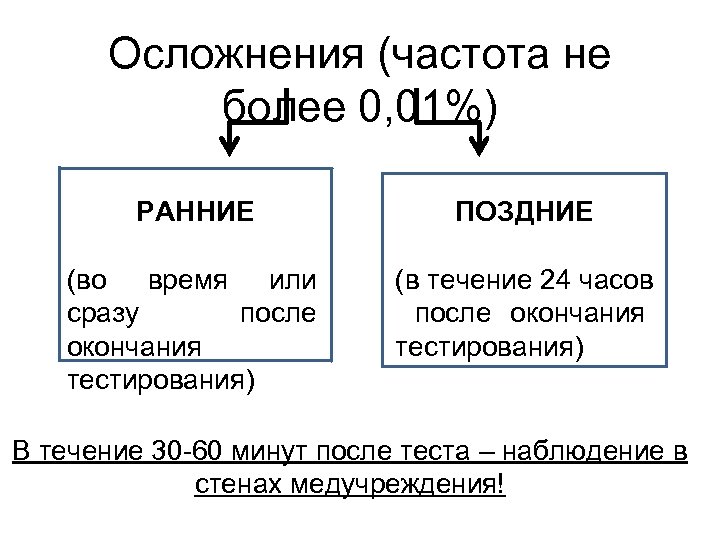

Осложнения (частота не более 0, 01%) РАННИЕ ПОЗДНИЕ (во время или сразу после окончания тестирования) (в течение 24 часов после окончания тестирования) В течение 30 -60 минут после теста – наблюдение в стенах медучреждения!

Осложнения (частота не более 0, 01%) РАННИЕ ПОЗДНИЕ (во время или сразу после окончания тестирования) (в течение 24 часов после окончания тестирования) В течение 30 -60 минут после теста – наблюдение в стенах медучреждения!

• Развитие типичного приступа стенокардии с самостоятельным или медикаментозным купированием болей и последующей нормализацией ЭКГ в течение пяти минут не является осложнением

• Развитие типичного приступа стенокардии с самостоятельным или медикаментозным купированием болей и последующей нормализацией ЭКГ в течение пяти минут не является осложнением